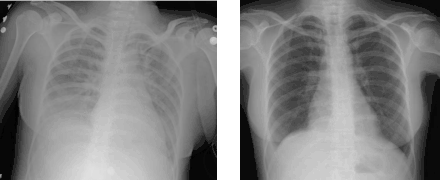

Medical imaging

Radiologic imaging has long been a criterion for diagnosis of ARDS. Original definitions of ARDS specified that correlative chest X-ray findings were required for diagnosis, the diagnostic criteria have been expanded over time to accept CT and ultrasound findings as equally contributory. Generally, radiographic findings of fluid accumulation (pulmonary edema) affecting both lungs and unrelated to increased cardiopulmonary vascular pressure (such as in heart failure) may be suggestive of ARDS.[20] Ultrasound findings suggestive of ARDS include the following:

- bilateral opacities on chest imaging (chest radiograph or CT) not explained by other lung pathology (e.g. effusion, lobar/lung collapse, or nodules)